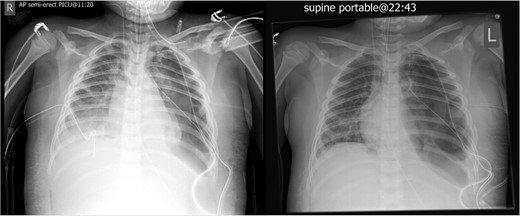

The initial chest radiograph revealed a possible diaphragmatic hernia and the patient was transferred to our institution for further investigation. The chest radiograph on arrival demonstrated a large air filled cavity at the left lung base. Further smaller cystic cavities were seen medially at the left base and right mid zone. The possible differential diagnoses included lung abscesses or diaphragmatic hernia (Fig. 1).

Chest radiograph on admission: a large air filled cavity at the left base. Further small cystic cavities seen medially at the left base and right mid to lower zone.